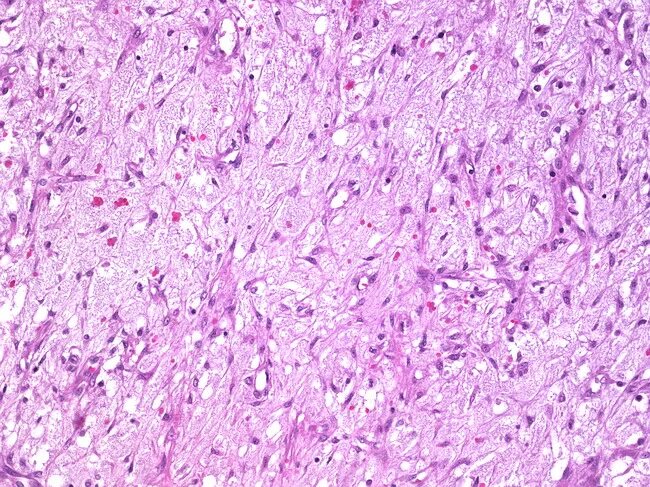

Гистология фиброзные фрагменты